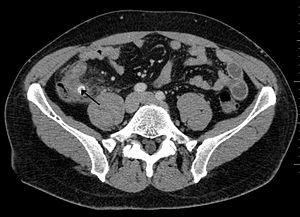

A fecalith is a stone made of feces. It is a hardening of feces into lumps of varying size and may occur anywhere in the intestinal tract but is typically found in the colon. It is also called appendicolith when it occurs in the appendix and is sometimes concomitant with appendicitis.[1] They can also obstruct diverticula. It can possibly form secondary to fecal impaction. A fecaloma is a more severe form of fecal impaction, and a hardened fecaloma may be considered to be a giant fecalith. The term is from Greek líthos=stone.[2]

A small fecalith is one cause of both appendicitis and acute diverticulitis.